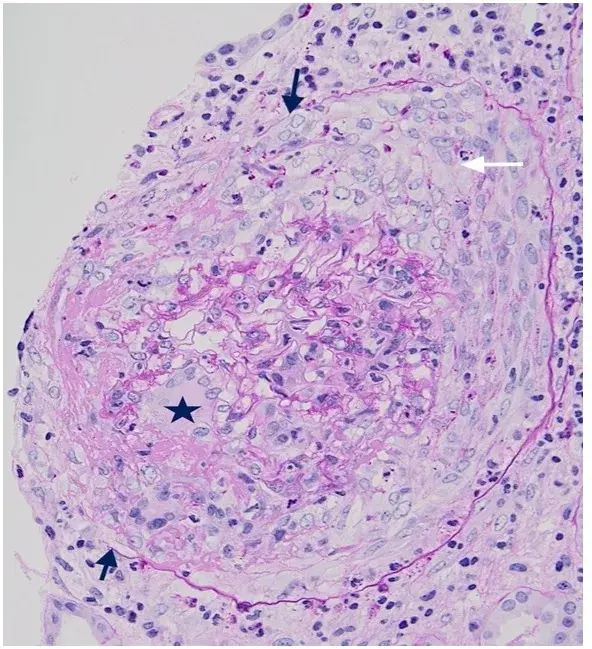

Es posible identificar un glomérulo con rotura de la membrana basal glomerular, con crecimiento celular en el espacio de Bowman (flecha blanca), células gigantes multinucleadas (estrella) y ruptura de la cápsula de Bowman (flecha negra) (tinción PAS; 400×). PAS, ácido periódico-Schiff.

La biopsia renal reveló GN (glomerulonefritis) crescéntica necrotizante difusa sin hipercelularidad endocapilar. Algunos raros glomérulos contenían células gigantes multinucleadas.

La evaluación de la microscopía de luz puede ayudar en la diferenciación entre casos de **GN por anti-MBG** y casos de **GN-ANCA**, ya que en la GN por anti-MBG no se observa hipercelularidad endocapilar y se puede identificar la presencia de células gigantes multinucleadas. Estas células gigantes multinucleadas resultan de la naturaleza explosiva y la rápida destrucción de los glomérulos observada en la anti-MBG.

Por lo tanto, la presencia de lesiones crescénticas temporalmente similares y células gigantes multinucleadas en la microscopía de luz (MO) puede ayudar en el diagnóstico temprano."